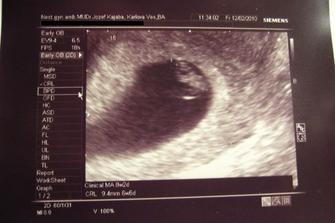

♥ 12.02.2010 sme boli na kontrolnom sone. Bábo zase krásne podrástlo a krásne mi zakývalo. Krvička nie je celkom v poriadku a čaká nás hematológia.